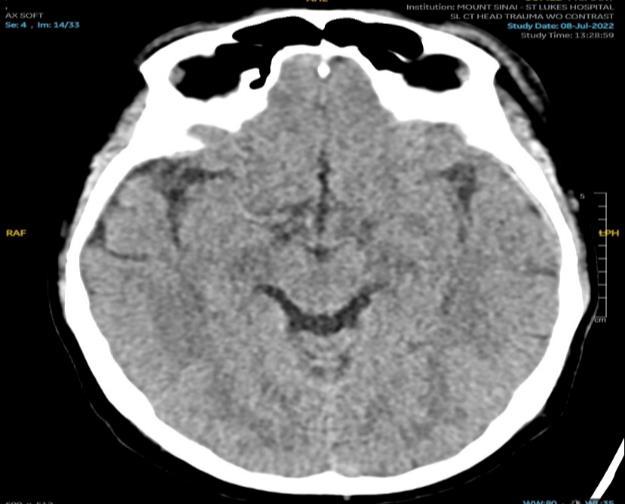

VALACYCLOVIR ASSOCIATED NEUROTOXICITY IN A PATIENT WITH END STAGE RENAL DISEASE

Venus Sharma1 , Rohit Rajesh Nathani1 , Ayush Gandhi1

1Mount Sinai Morningside-West Hospitals, Icahn School of Medicine at Mount Sinai, New York, NY, United States